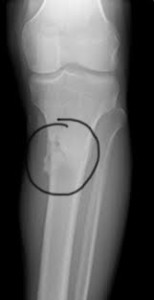

Συμπτώματα κατάγματος της κνήμης

Ασθενείς με κάταγμα της κνήμης παραπονιούνται για αυξανόμενο πόνο στην έσω περιοχή της κνήμης. Ο πόνος είναι συνήθως οξύς και απότομος, αυξάνεται κατά την κρούση και ελαττώνεται με την ανάπαυση. Σε προχωρημένο στάδιο, ακόμα και η βάδιση επιδεινώνει την κατάσταση. Ακόμα, πολύ συχνά το κάταγμα της κνήμης παρουσιάζεται σαν πόνος στο πίσω μέρος της κνήμης (γαστροκνήμιο) ή στην πρόσθια επιφάνεια της κνήμης αντί για το εσωτερικό.